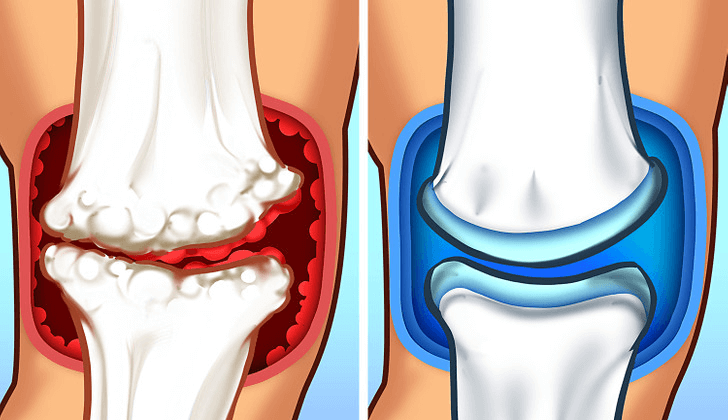

Wanneer gewrichtsweefsels ontstoken raken, hopen afvalproducten zich op, waardoor een "afvalbarrière" dat verhindert genezing.

Deze barrière:

- Houdt ontstekingsstoffen vast die 's nachts pijnreceptoren stimuleren

- Voorkomt dat slaapbevorderende voedingsstoffen de aangetaste weefsels bereiken

- Creëert een constante irritatie die vooral merkbaar is als je probeert te rusten

Deze afvalbarrière verklaart waarom zelfs krachtige slaap- en pijnstillers vaak falen – ze pakken deze fundamentele blokkade niet aan.

Stap 1: Maak de afvalbarrière leeg

De eerste doorbraak kwam door het bestuderen van mensen met een uitzonderlijke levensduur en slaapkwaliteit, waarbij vooral werd gekeken naar stoffen die de bloedsomloop naar gewrichtsweefsels verbeteren.

De belangrijkste ontdekking was OPC (oligomere proanthocyanidinen) uit druivenpitten, welke verbetert de bloedvloeibaarheid en versterkt de vaatwanden, waardoor uw lichaam afvalproducten uit de gewrichten kan verwijderen en slaapbevorderende voedingsstoffen effectiever kan transporteren.

Dit krachtige antioxidant lost de afvalbarrière op die ervoor zorgt dat pijnsignalen de hele nacht blijven vuren.